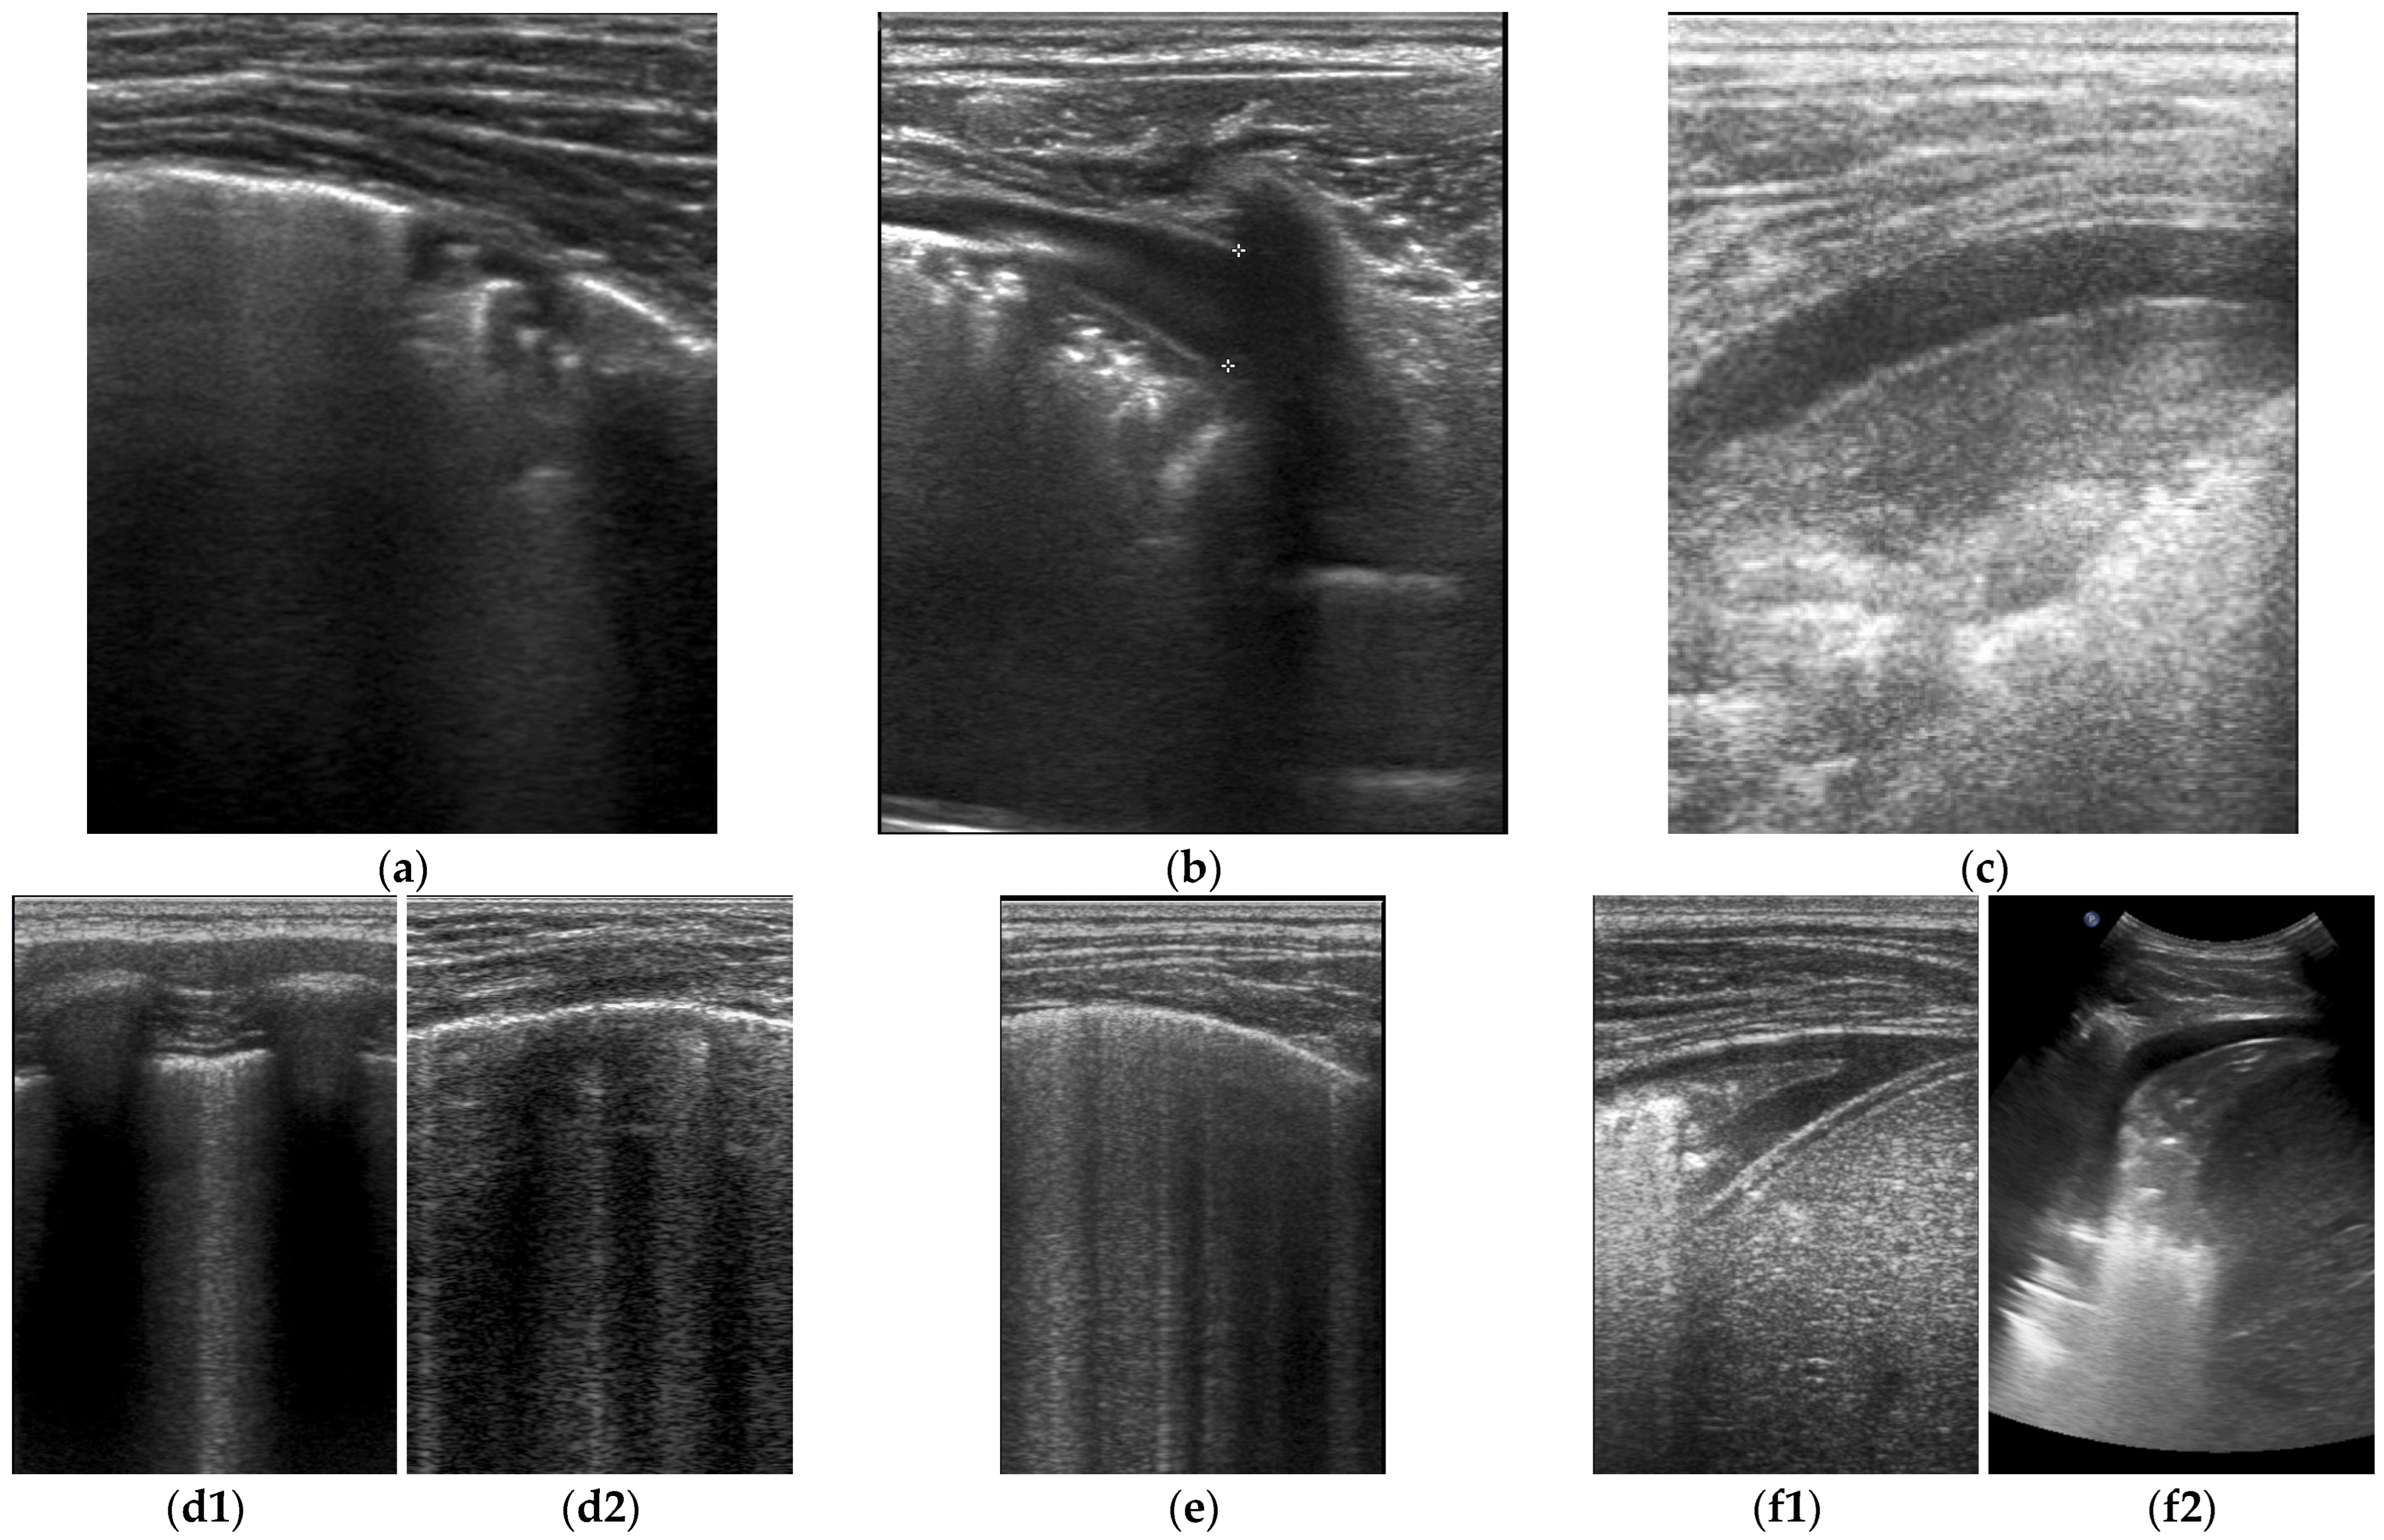

3. Results

4. Discussion